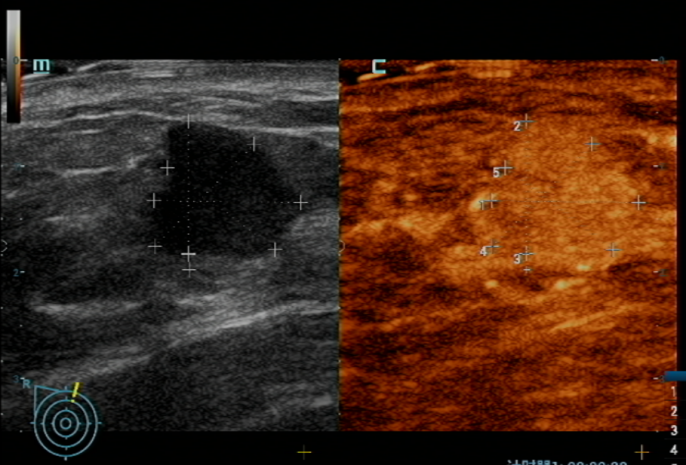

黄女士因“右侧乳房肿物”就诊于我院,经影像学检查及穿刺活检,确诊为右侧乳腺浸润性癌。

在陈伦主任与我院普外科团队的密切配合下,手术顺利开展。不同于传统乳腺癌根治术,此次采用的保乳手术仅切除肿瘤及周围少量组织,最大程度保留了乳房外形;同时通过前哨淋巴结活检术,精准检测腋窝淋巴结转移情况(仅1枚阳性),避免了全腋窝清扫可能导致的上肢水肿、活动受限等并发症。

术后病理证实:肿瘤完整切除,所有手术切缘(10个切缘)未见癌细胞残留,达到“根治性切除”标准。这种“精准微创”理念,不仅减少了手术创伤,更为患者后续康复和生活质量奠定了基础。